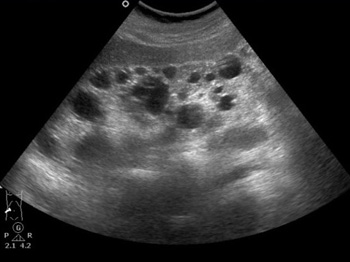

Canon PVT-375BT |

Конвексный |

1,5-6 МГц |

Абдоминальные обследования(печень, желчный пузырь, селезенка, поджелудочная железа, глубокие сосуды) Акушерство и гинекология |

Canon PVT-475BT (8C1) |

Конвексный |

1,5-6 МГц |

Абдоминальные обследования(печень, желчный пузырь, селезенка, поджелудочная железа, глубокие сосуды) Акушерство и гинекология |

Canon PVT-375SC (6Cs1) |

Конвексный |

1,5-6 МГц |

Абдоминальные обследования(печень, желчный пузырь, селезенка, поджелудочная железа, глубокие сосуды) Акушерство и гинекология |

Canon PVT-674BT (10C3) |

Конвексный |

3,3-9,2 МГц |

Абдоминальные обследования(печень, желчный пузырь, селезенка, поджелудочная железа, глубокие сосуды) Акушерство и гинекология |